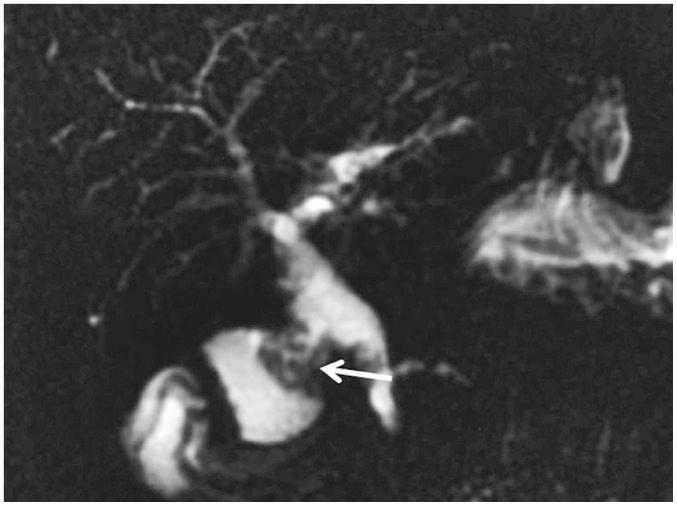

This pictorial review aims to illustrate the magnetic resonance imaging (MRI) findings and presentation patterns of anatomical variations and various benign and malignant pathologies of the duodenum, including sphincter contraction, major papilla variation, prominent papilla, diverticulum, annular pancreas, duplication cysts, choledochocele, duodenal wall thickening secondary to acute pancreatitis, postbulbar stenosis, celiac disease, fistula, choledochoduodenostomy, external compression, polyps, Peutz-Jeghers syndrome, ampullary carcinoma and adenocarcinoma. MRI is a useful imaging tool for demonstrating duodenal pathology and its anatomic relationships with adjacent organs, which is critical for establishing correct diagnosis and planning appropriate treatment, especially for surgery.